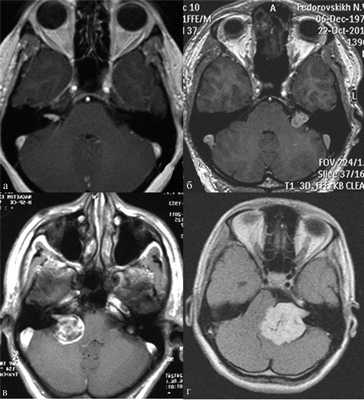

В практической деятельности наиболее универсальными являются классификации, предложенные Koos [11] и Samii [12]. Они основаны на оценке размеров невриномы и ее отношении к окружающим мозговым и костным структурам (рис. 1, 2).

Рис. 1.Иллюстрация классификации неврином слухового нерва по Koos. а — I стадия — опухоль находится в пределах внутреннего слухового прохода, диаметр экстраканальной части составляет 1—10 мм; б — II стадия — опухоль вызывает расширение канала внутреннего слухового прохода и выходит в мостомозжечковый угол, ее диаметр составляет, 11—20 мм; в — III стадия — опухоль распространяется до ствола головного мозга без его компрессии, диаметр составляет 21—30 мм; г — IV стадия — опухоль вызывает компрессию ствола головного мозга, ее диаметр более 30 мм.

Рис. 2.Классификация неврином слухового нерва по M. Samii. а — Т1 — интрамеатальная опухоль (рис. 2, a); б —Т2 — интра-экстрамеатальная опухоль; в — Т3а — опухоль заполняет мостомозжечковую цистерну; г —Т3b — опухоль распространяется до ствола головного мозга; д —Т4а — опухоль вызывает компрессию ствола; е —Т4b — опухоль грубо деформирует ствол мозга и IV желудочек.

В клинической практике обе эти классификации следует равноценно рассматривать в качестве основных принципов оценки клинической стадии заболевания (опция).